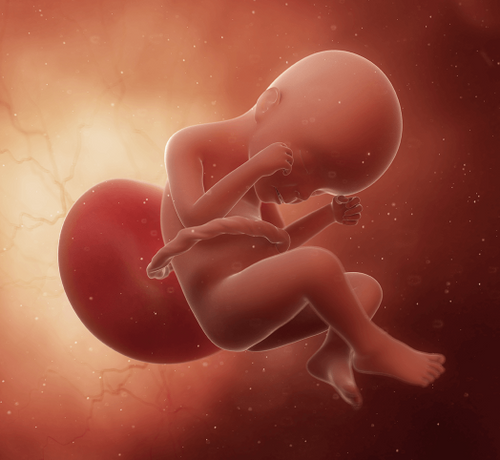

Hafta Hafta Gebelik

Hamileliğinizin her haftasında sizi nelerin beklediğini öğrenin. Hafta hafta gebelik yazılarımızla bebeğinizin gelişimini takip edin, vücudunuzdaki değişimleri keşfedin ve sağlıklı bir hamilelik süreci geçirin.

Hamileliğinizin her haftasında sizi nelerin beklediğini öğrenin. Hafta hafta gebelik yazılarımızla bebeğinizin gelişimini takip edin, vücudunuzdaki değişimleri keşfedin ve sağlıklı bir hamilelik süreci geçirin.